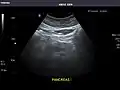

Abdominal Ultrasound (Full Exam)

STRUCTURED REPORT

(Technique: Transabdominal ultrasonography; Device: Toshiba Aplio XG)

Liver: Diffusely homogeneous and normal in echogenicity. No focal mass or contour nodularity. No intrahepatic biliary ductal dilatation.

Portal Vein: Patent main portal vein.

Gallbladder: No stones, wall thickening, or pericholecystic fluid.

Common Bile Duct: Nondilated measuring 1.3 mm at the level of the porta hepatis.

Pancreas: Visualized portions unremarkable.

Spleen: Normal in size.

Kidneys: Right and left kidneys measure 11.5 cm and 12 cm in length respectively. No hydronephrosis. Small left lower pole kidney cyst.

Ascites: None.

Aorta: Visualized portions normal in caliber, 16 x 15 mm.

IVC: Normal.

IMPRESSION:

Normal abdominal ultrasound.

Pancreas